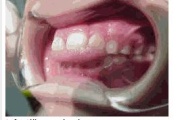

Ruumipuudus eesmiste hammaste osas